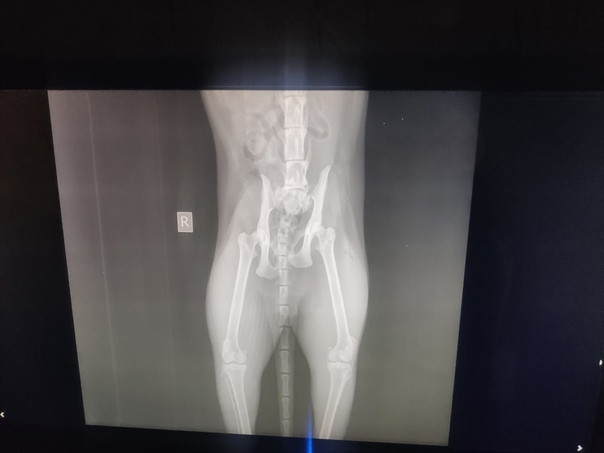

В ночь с 08 на 09 ноября собаки зверски истерзали кота. Мы сразу же поехали в ветеринарную клинику ("Зоосити Лайф", просп. Победы, 18Б), там поставили диагноз перелом позвоночника и перелом тазобедренного сустава.

❗Нужно делать срочную операцию на позвоночник (с установкой транспедикулярных винтов), такую операцию делают всего в трех клиниках Казани, также нужна операция по восстановлению тазобедренного сустава и ампутация хвоста. У кота полностью не двигается задняя часть туловища.